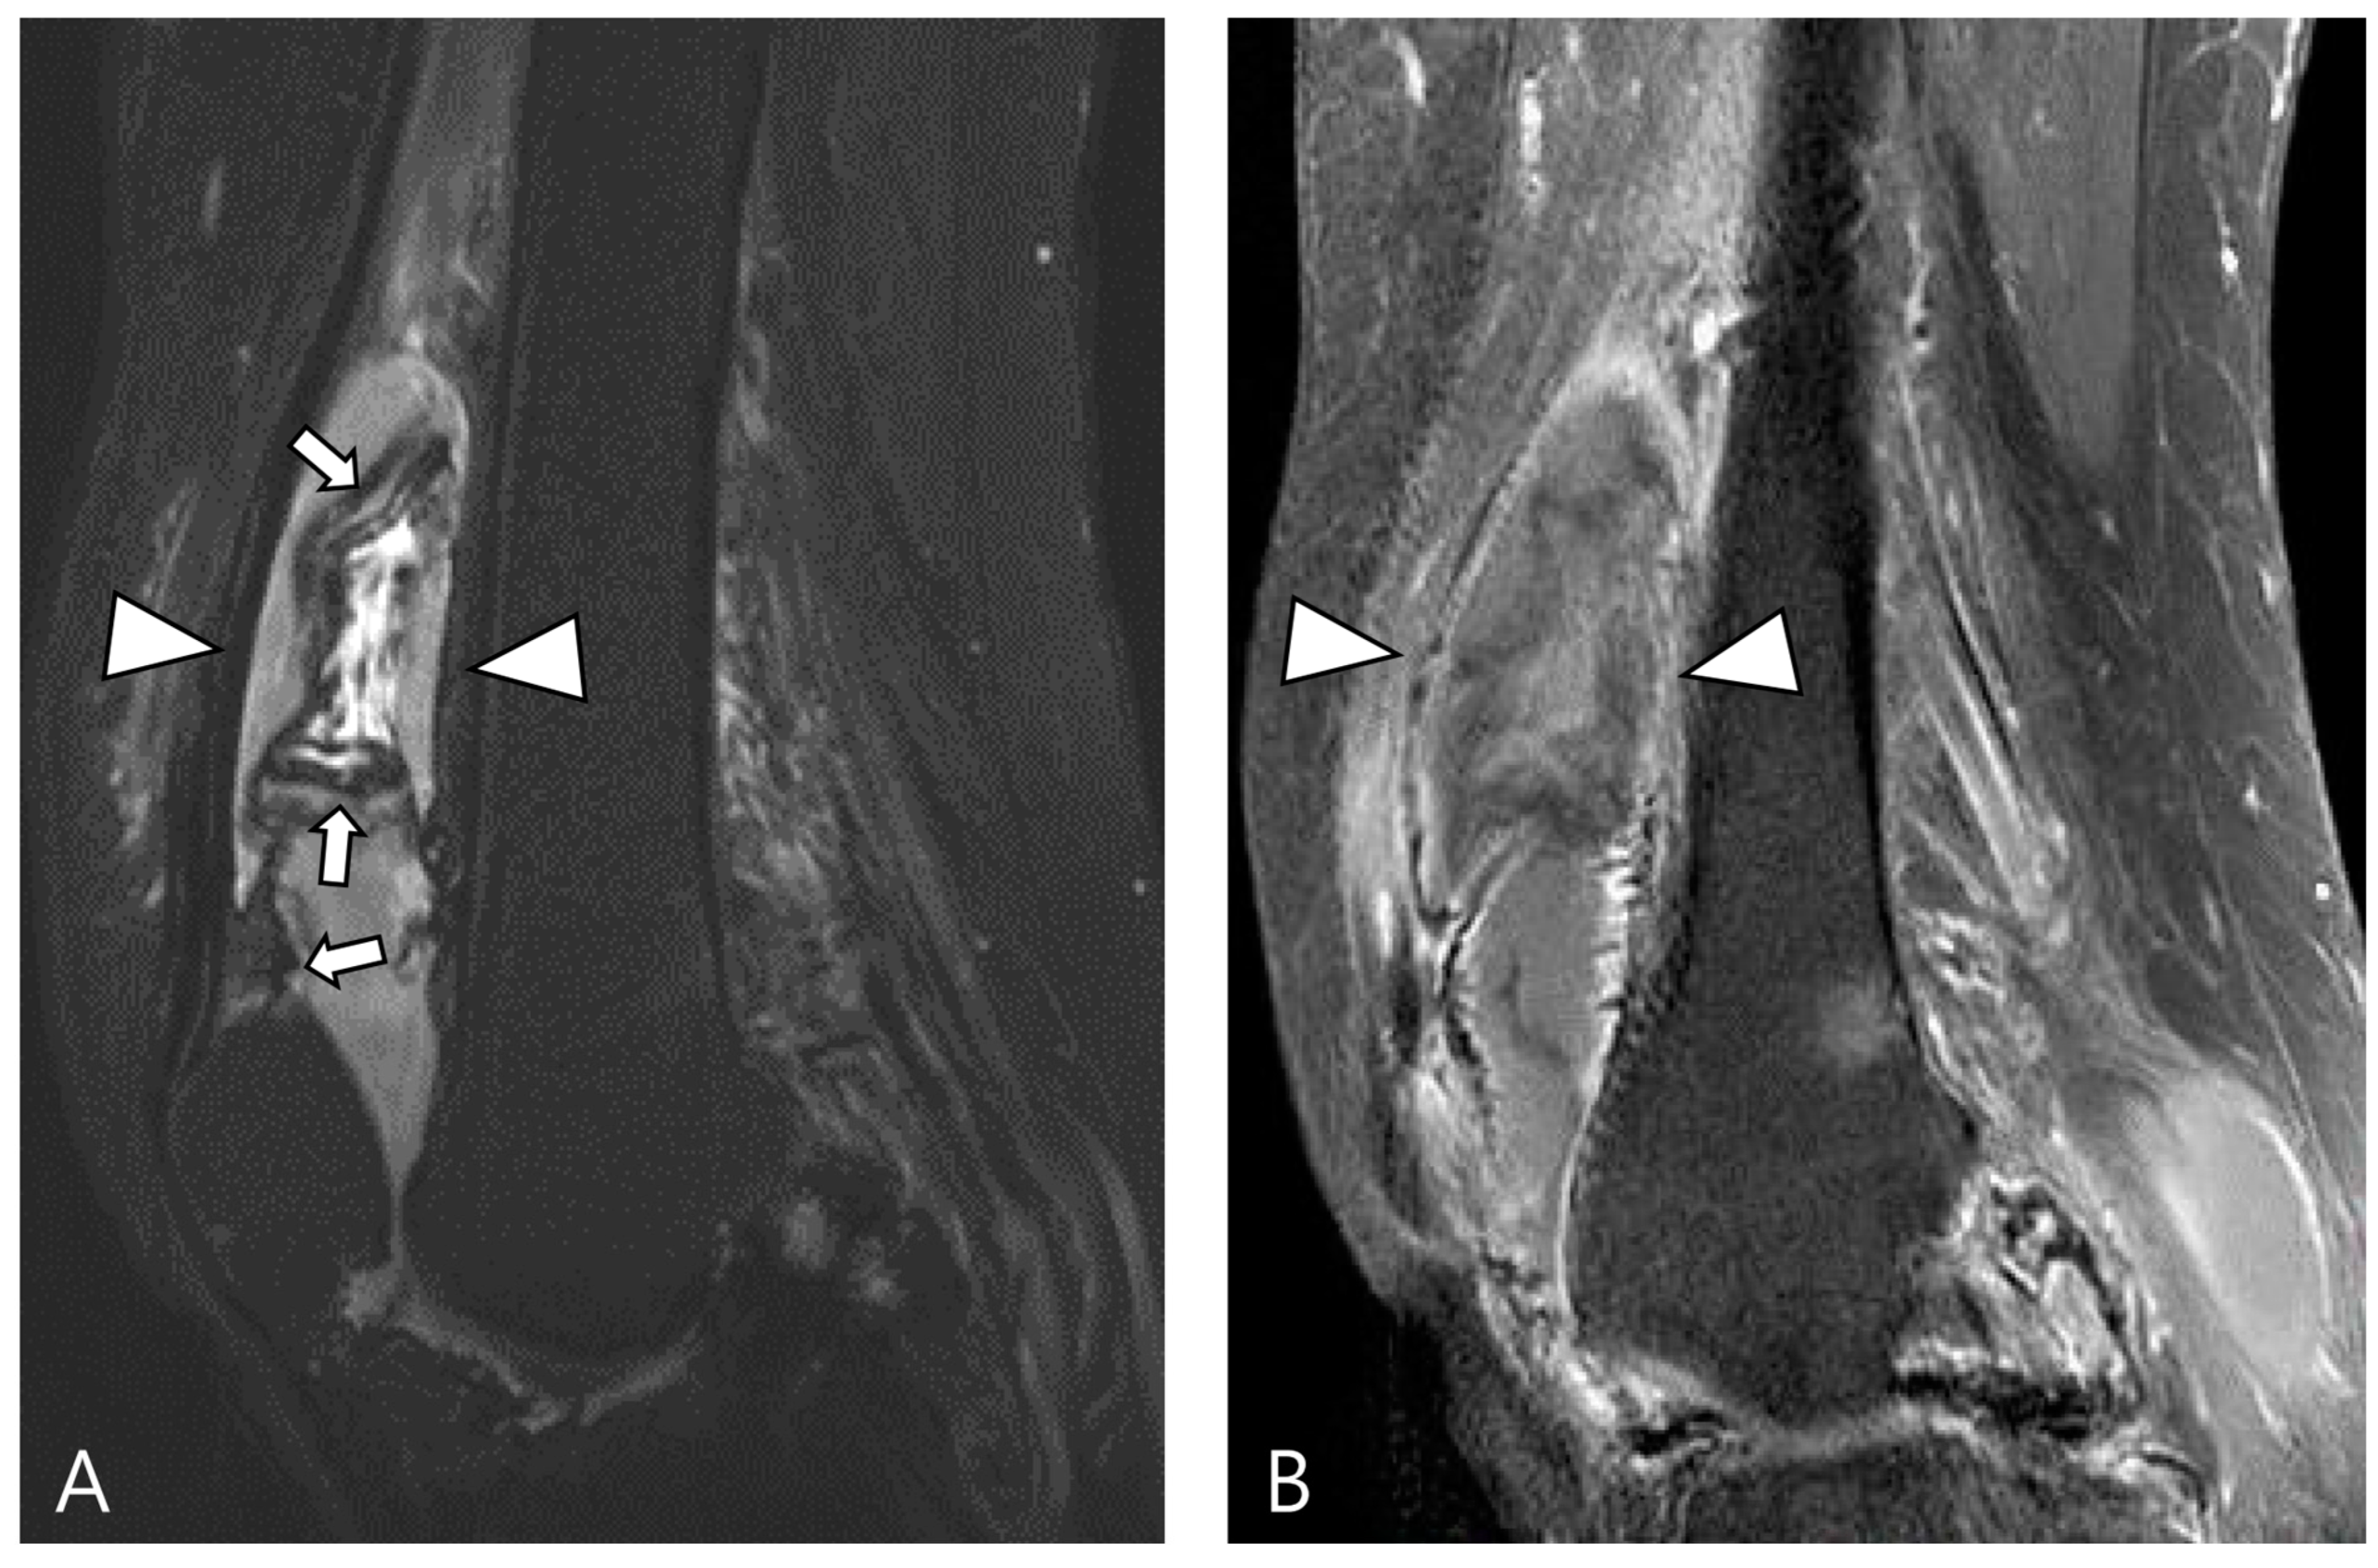

2.4. Relationship to Adjacent Structures of D-TSGCT